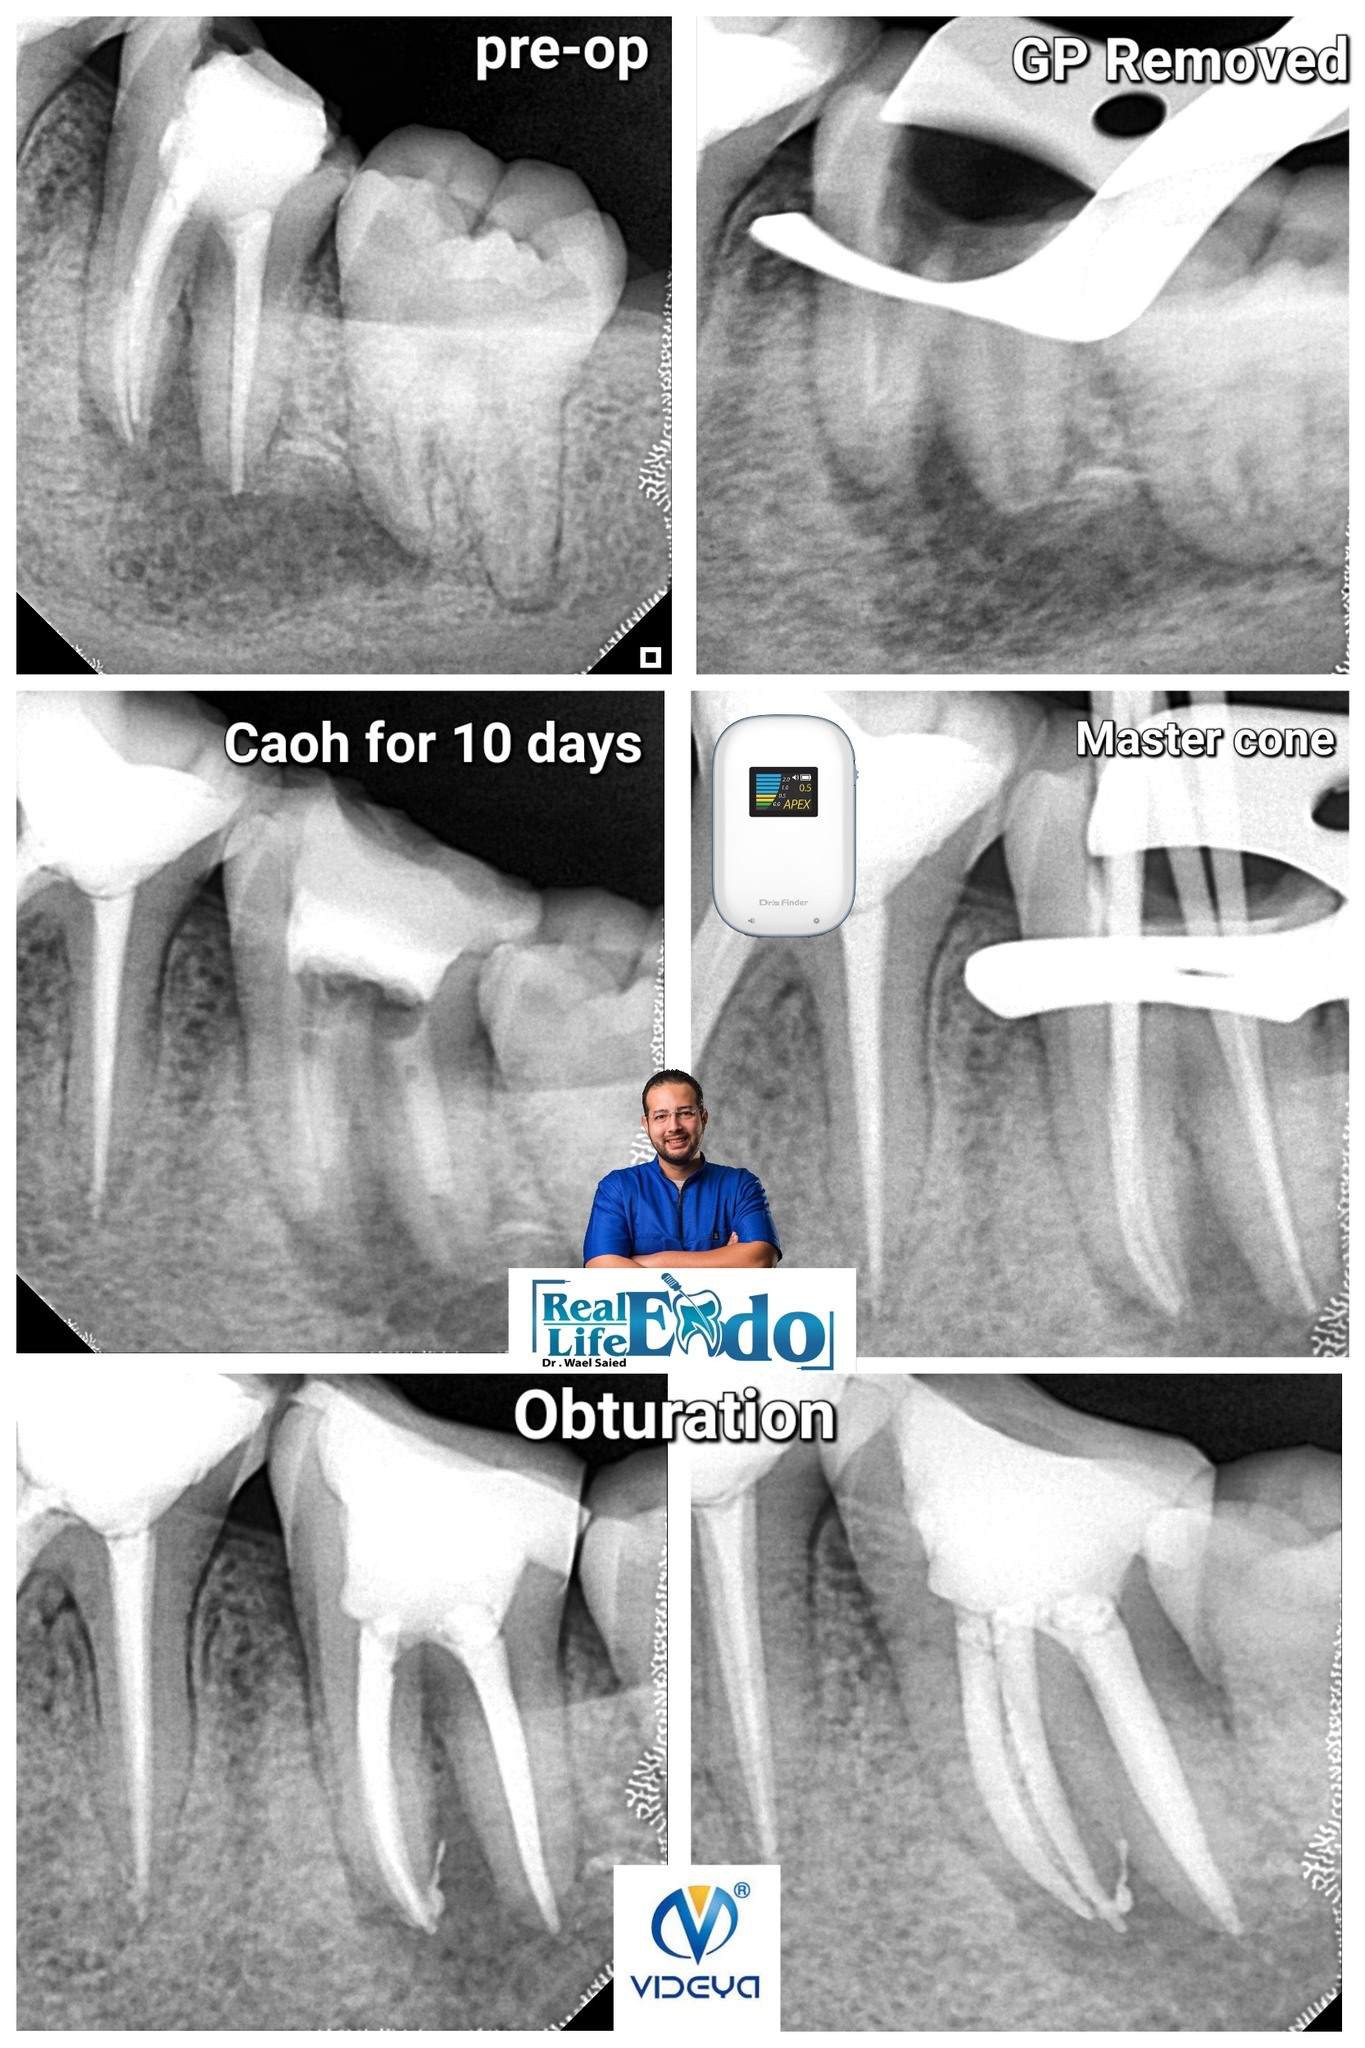

Lower 2nd Molar with chronic periapical abscess and gingival swelling

A great sign of healing and success is disappearing of swelling or fistula after only shaping... irrigation and Caoh placement

in this case:

1st visit.. Access...Gp Removal...Shaping…..Irrigation... Caoh Placement

2nd visit (After 10 days) ... Irrigation and obturation

Shaping with Videya Dental Rainbow Files